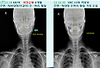

68/여 파킨슨병으로 약물치료중 6개월 SNC10회 치료후 사진비교

작성자

나인석

작성시간

14.04.24

조회수

846